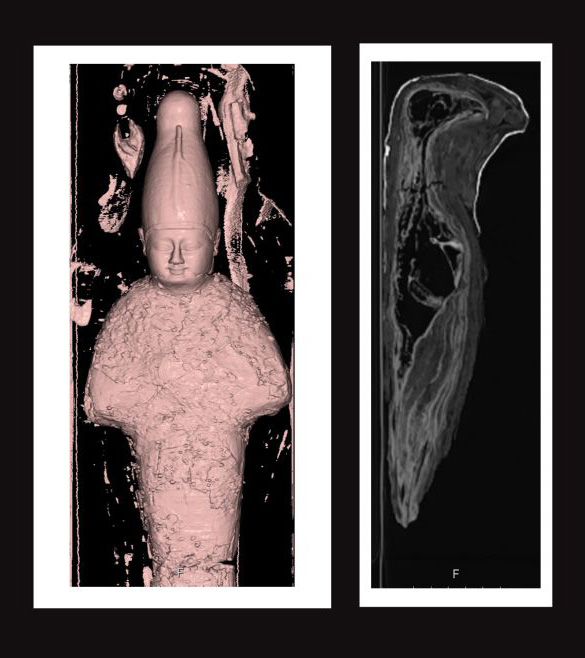

The CT scans done at Rambam Hospital revealed that the mummies had very different insides from one another. The roughly 18-inch-long (45 centimeters) human-shaped mummy — designed to look like Osiris, the god of the afterlife, the dead, life, and vegetation — contained mud and grains.

The other mummy, a roughly 10-inch-long (25 cm) bird-shaped mummy, represented the god Horus. According to Egypt mythology, Horus was the falcon-headed son of Osiris and Isis; a deity associated with the sky and pharaohs.

Over time, the bird mummy had desiccated, meaning that the tissue got more dense, like beef jerky. Meanwhile, the marrow in the bones had dried out, leaving nothing but delicate bone tubes.

So Javitt and her colleagues used a dual-energy CT, which uses both normal X-rays and less powerful X-rays, a technique that can reveal properties of the tissues that a regular CT scan can’t, Javitt said.

Now, her team is identifying the bird’s various tissues and bones. Javitt noted that the bird’s neck is broken, but that this injury likely happened after the bird was dead. That’s because the skin is broken too, and in most cases of broken bones, “you don’t usually crack open the skin from one edge to the opposite side, you just break the bone,” Javitt said.

Moreover, the bird appears to be missing some of its abdominal organs, but more study is needed to determine which ones aren’t there, she said. For instance, the heart appears to be present, as is the trachea.